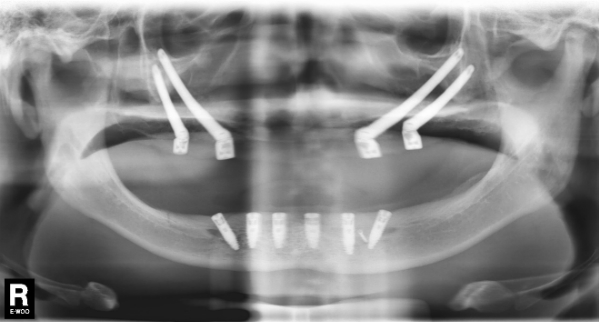

Bệnh nhân Kim (30 tuổi, quê Hà Nội) không có đầy đủ răng, các răng đã mọc có hình cọc, yếu. Chị phải đeo răng giả từ khi 14 tuổi khiến xương hàm trên và hàm dưới bị tiêu trầm trọng sát đáy xoang hàm, thậm chí còn lộ dây thần kinh. Để giải quyết trường hợp này, Ts.Bs Võ Văn Nhân đã phẫu thuật dời dây thần kinh hàm dưới (*) và cấy ghép implant xương gò má (*) để trồng răng hai hàm cho bệnh nhân.

Kết quả trồng răng cho bệnh nhân Kim

Trường hợp thứ hai là bệnh nhân Lý (23 tuổi, Đồng Nai). Lý không có răng bẩm sinh, phải đeo hàm giả từ năm 10 tuổi. Đây là một trong những dạng nghiêm trọng của hội chứng loạn sản ngoại bì, rất hiếm gặp với tỷ lệ 1/100 000 người mắc phải.

Tình trạng răng của bệnh nhân Lý